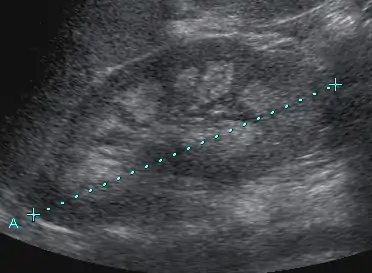

- Medullary nephrocalcinosis in Sonography

Nephrocalcinosis is diagnosed for the most part by imaging techniques. The imagings used are ultrasound (US), abdominal plain film and CT imaging.[11] Of the 3 techniques CT and US are the more preferred. Nephrocalcinosis is considered present if at least two radiologists make the diagnosis on US and/or CT. In some cases a renal biopsy is done instead if imaging is not enough to confirm nephrocalcinosis. Once the diagnosis is confirmed additional testing is needed to find the underlying cause because the underlying condition may require treatment for reasons independent of nephrocalcinosis.[11] These additional tests will measure serum, electrolytes, calcium, and phosphate, and the urine pH.[11] If no underlying cause can be found then urine collection should be done for 24 hours and measurements of the excretion of calcium, phosphate, oxalate, citrate, and creatinine are looked at.[11]